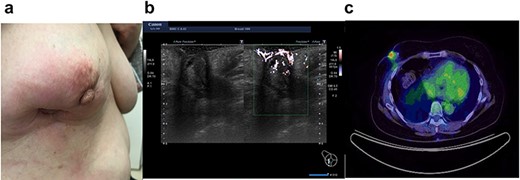

In 2020, she complained of right breast pain. She also noticed erythematous changes of the skin on her right breast. Examination revealed a right breast tumor at the site of the surgical scar with markedly erythematous changes of the skin (Fig. 3a). Ultrasound revealed a hypoechoic cystic mass, resembling a chronic abscess with thick skin. The cystic nature of the tumor suggested the possibility of recurrence of breast cancer (Fig. 3b). PET-CT revealed a right breast tumor and no distant metastasis, which was suspicious of local recurrence (Fig. 3c). Laboratory investigation indicated a C-reactive protein level of 2.3 mg/L and white blood cell count of 8770/mL. She was administered antibiotic therapy, consisting of cefaclor for 7 days, which resulted in the disappearance of the erythema. Subsequently, she underwent vacuum-assisted core needle biopsy (VACNB) of the wall of the cystic tumor. Pathology finding was a xanthogranulomatous inflammation and necrotic tissue with scar formation without any evidence of malignancy (Fig. 4). Additional VACNB was performed, which showed no malignancy. She elected not to undergo excision biopsy. Follow-up ultrasonography performed after 1.5 months, VACNB revealed no abnormal findings.

Case 3 presented with erythematous changes in the skin of the right breast (a). Ultrasound evaluation revealed a mixed pattern mass lesion 26.3 × 34.8 × 25.0 mm in the right breast (b), and PET-CT showed a right breast mass with an SUV max of 4.0 (c).